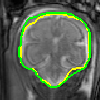

Despite the state-of-the-art performance for medical image segmentation, deep convolutional neural networks (CNNs) have rarely provided uncertainty estimations regarding their segmentation outputs, e.g., model (epistemic) and image-based (aleatoric) uncertainties. In this work, we analyze these different types of uncertainties for CNN-based 2D and 3D medical image segmentation tasks. We additionally propose a test-time augmentation-based aleatoric uncertainty to analyze the effect of different transformations of the input image on the segmentation output. Test-time augmentation has been previously used to improve segmentation accuracy, yet not been formulated in a consistent mathematical framework. Hence, we also propose a theoretical formulation of test-time augmentation, where a distribution of the prediction is estimated by Monte Carlo simulation with prior distributions of parameters in an image acquisition model that involves image transformations and noise. We compare and combine our proposed aleatoric uncertainty with model uncertainty. Experiments with segmentation of fetal brains and brain tumors from 2D and 3D Magnetic Resonance Images (MRI) showed that 1) the test-time augmentation-based aleatoric uncertainty provides a better uncertainty estimation than calculating the test-time dropout-based model uncertainty alone and helps to reduce overconfident incorrect predictions, and 2) our test-time augmentation outperforms a single-prediction baseline and dropout-based multiple predictions.